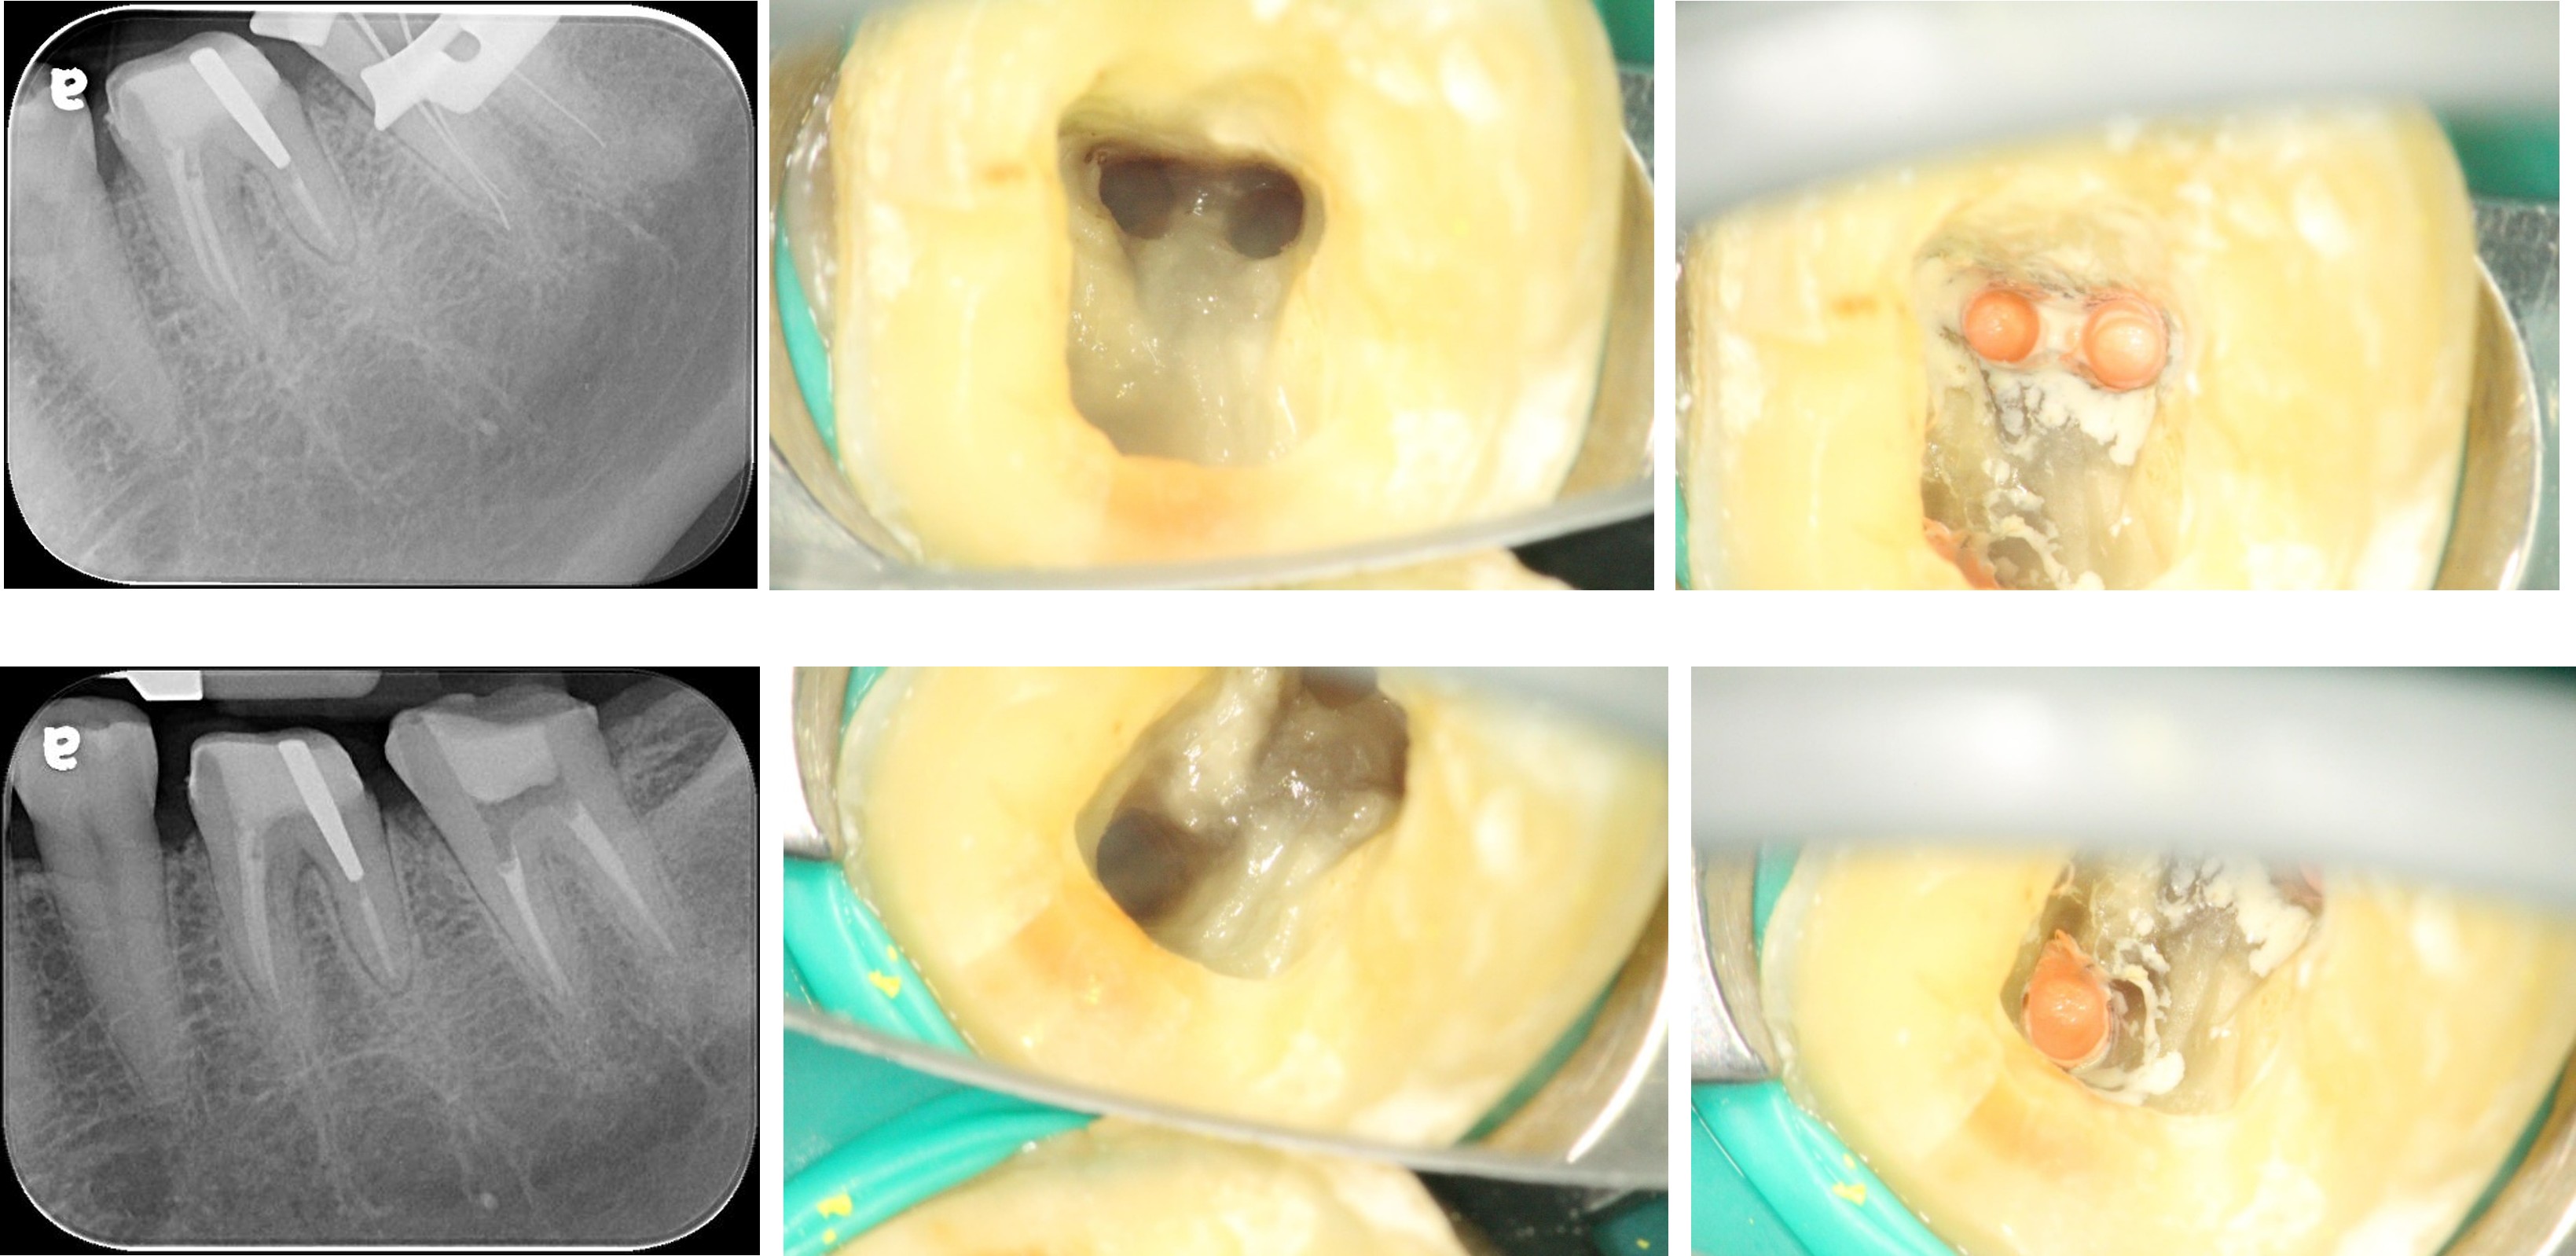

大臼齒顯微根管治療

鑄造陶瓷釘柱製作